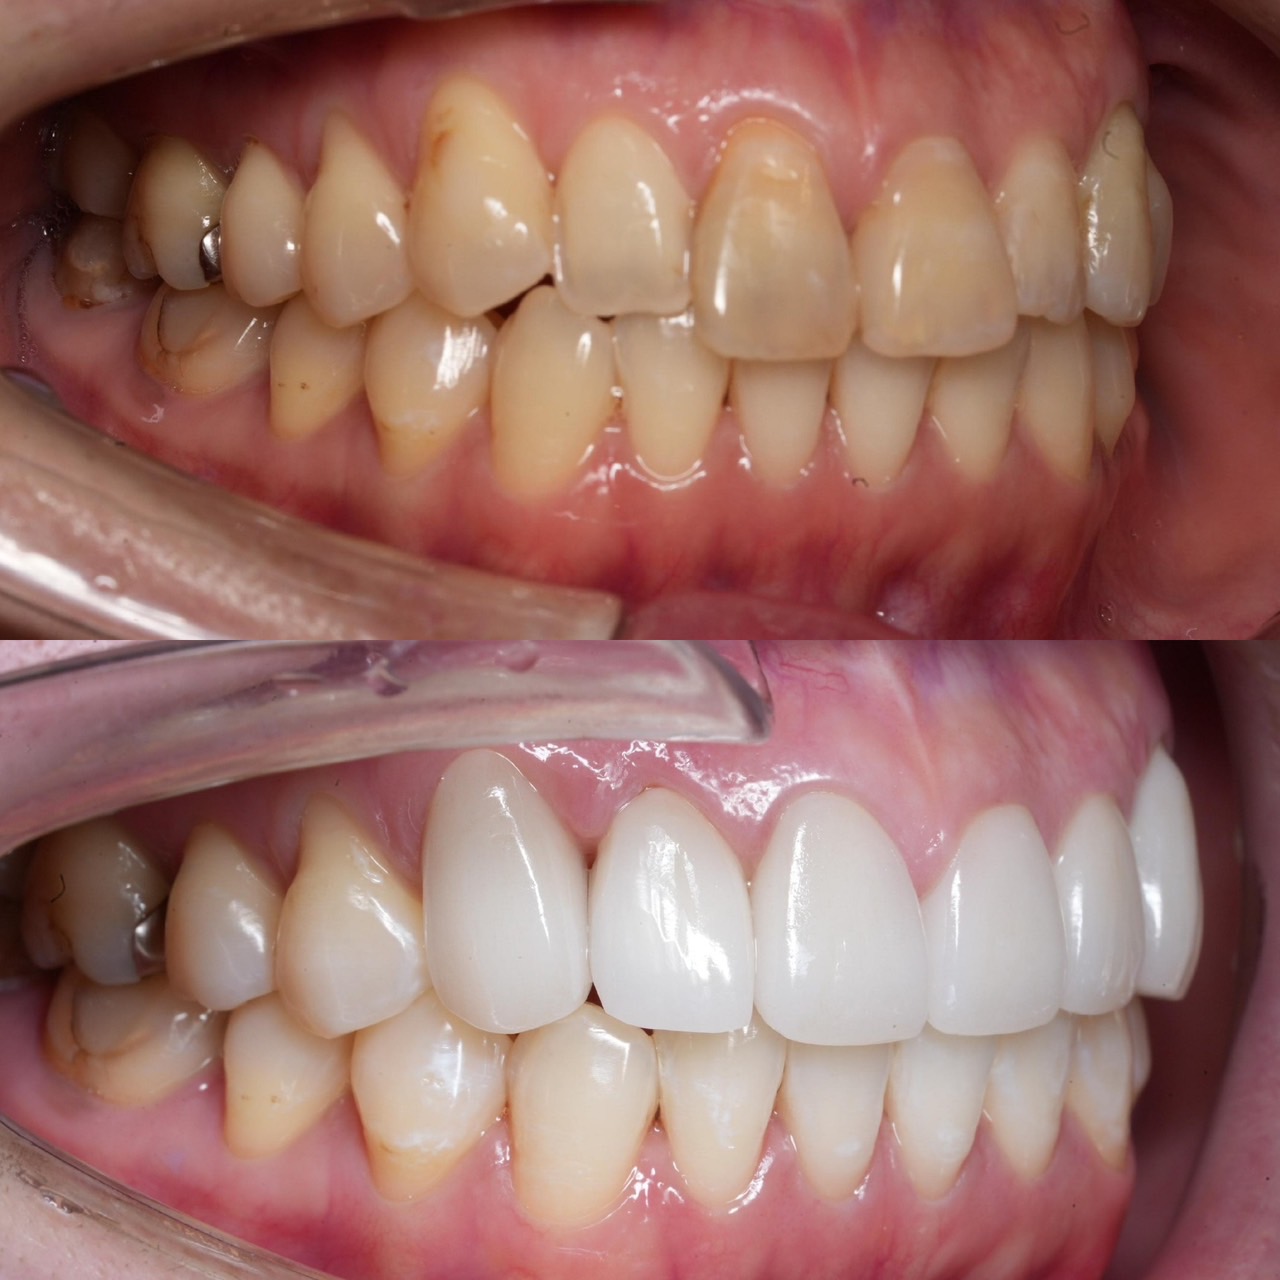

Case019

ずっと歯を治したかったけれど、時間がなくてできなかった方がようやく時間が取れるようになり、今回はしっかり治したいということで、ご来院頂けました。

初診時は全く噛めないくらい噛み合わせも悪くなってしまっていたのと、骨がないためにインプラントをするにも難しい状態でしたが、外見も爽やかに、食事も気にせず肉でも何でも噛めて、健康的な状態を目指して治療しました。

歯が綺麗になっていくにつれて笑顔も増えて、どんどん若々しくなっていくのを見てると歯科医としての仕事に本当にやりがいを感じました。

担当 理事長 佐藤 悠野